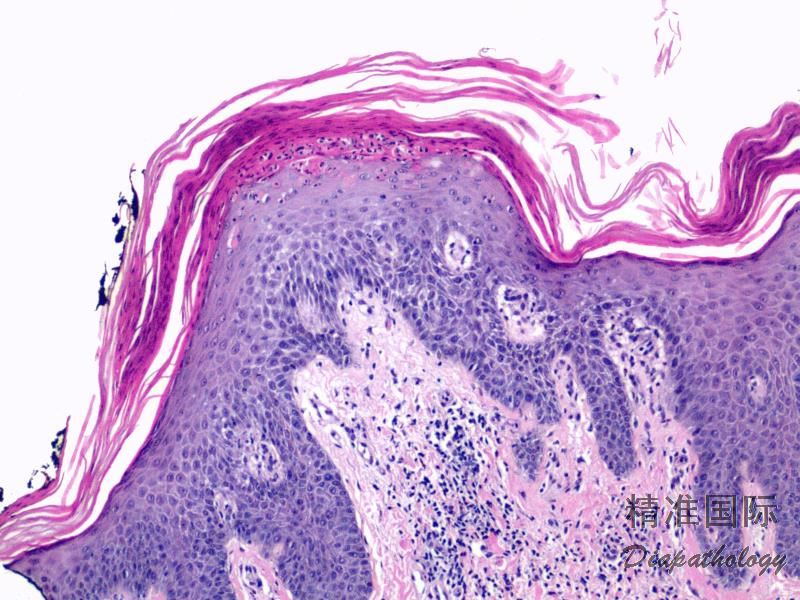

银屑病通常根据临床表现即可诊断,无需活检或辅助检查,临床表现典型时可行组织学检查。组织学改变:充分发展的斑块表现为角化不全伴中性粒细胞浸润、上皮脚明显规则性延长、颗粒层减少、乳头层上方表皮变薄、真皮乳头内血管扩张、迂曲及真皮浅层血管周围淋巴细胞为主的炎症细胞浸润。急性、点滴型或脓疱型皮损表现为中性粒细胞性海绵水肿、海绵水肿性脓疱(Kogoj 微脓疡,指表皮内中性粒细胞的聚集,可位于基底层、棘细胞层或颗粒层)及 Munro 微脓疡(指中性粒细胞在角质层内聚集)。中性粒绑胞在表皮内聚集很明显,但在真皮内并不多见。嗜酸性粒细胞在银屑病中通常不多见。